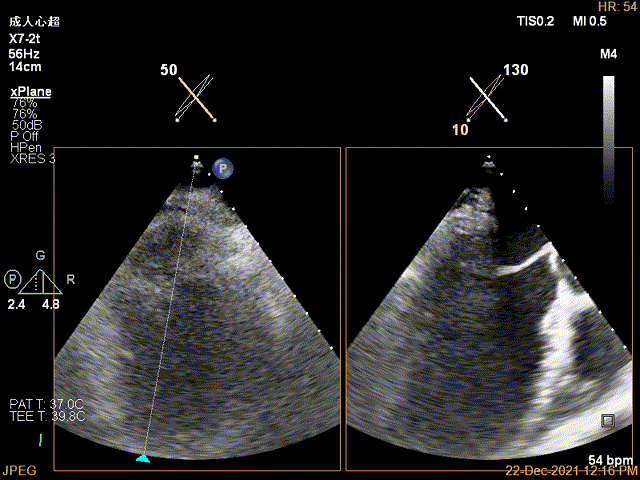

TEE Bicom view:二尖瓣后叶P2区大范围脱垂,部分累及1区及3区

Color-view:极大量反流,主要来源于2区

X-plane:下夹子尝试先捕获2区偏内侧瓣叶

夹子关闭过程中,Color提示2区反流逐渐减少,残余反流位于第一个夹子外侧